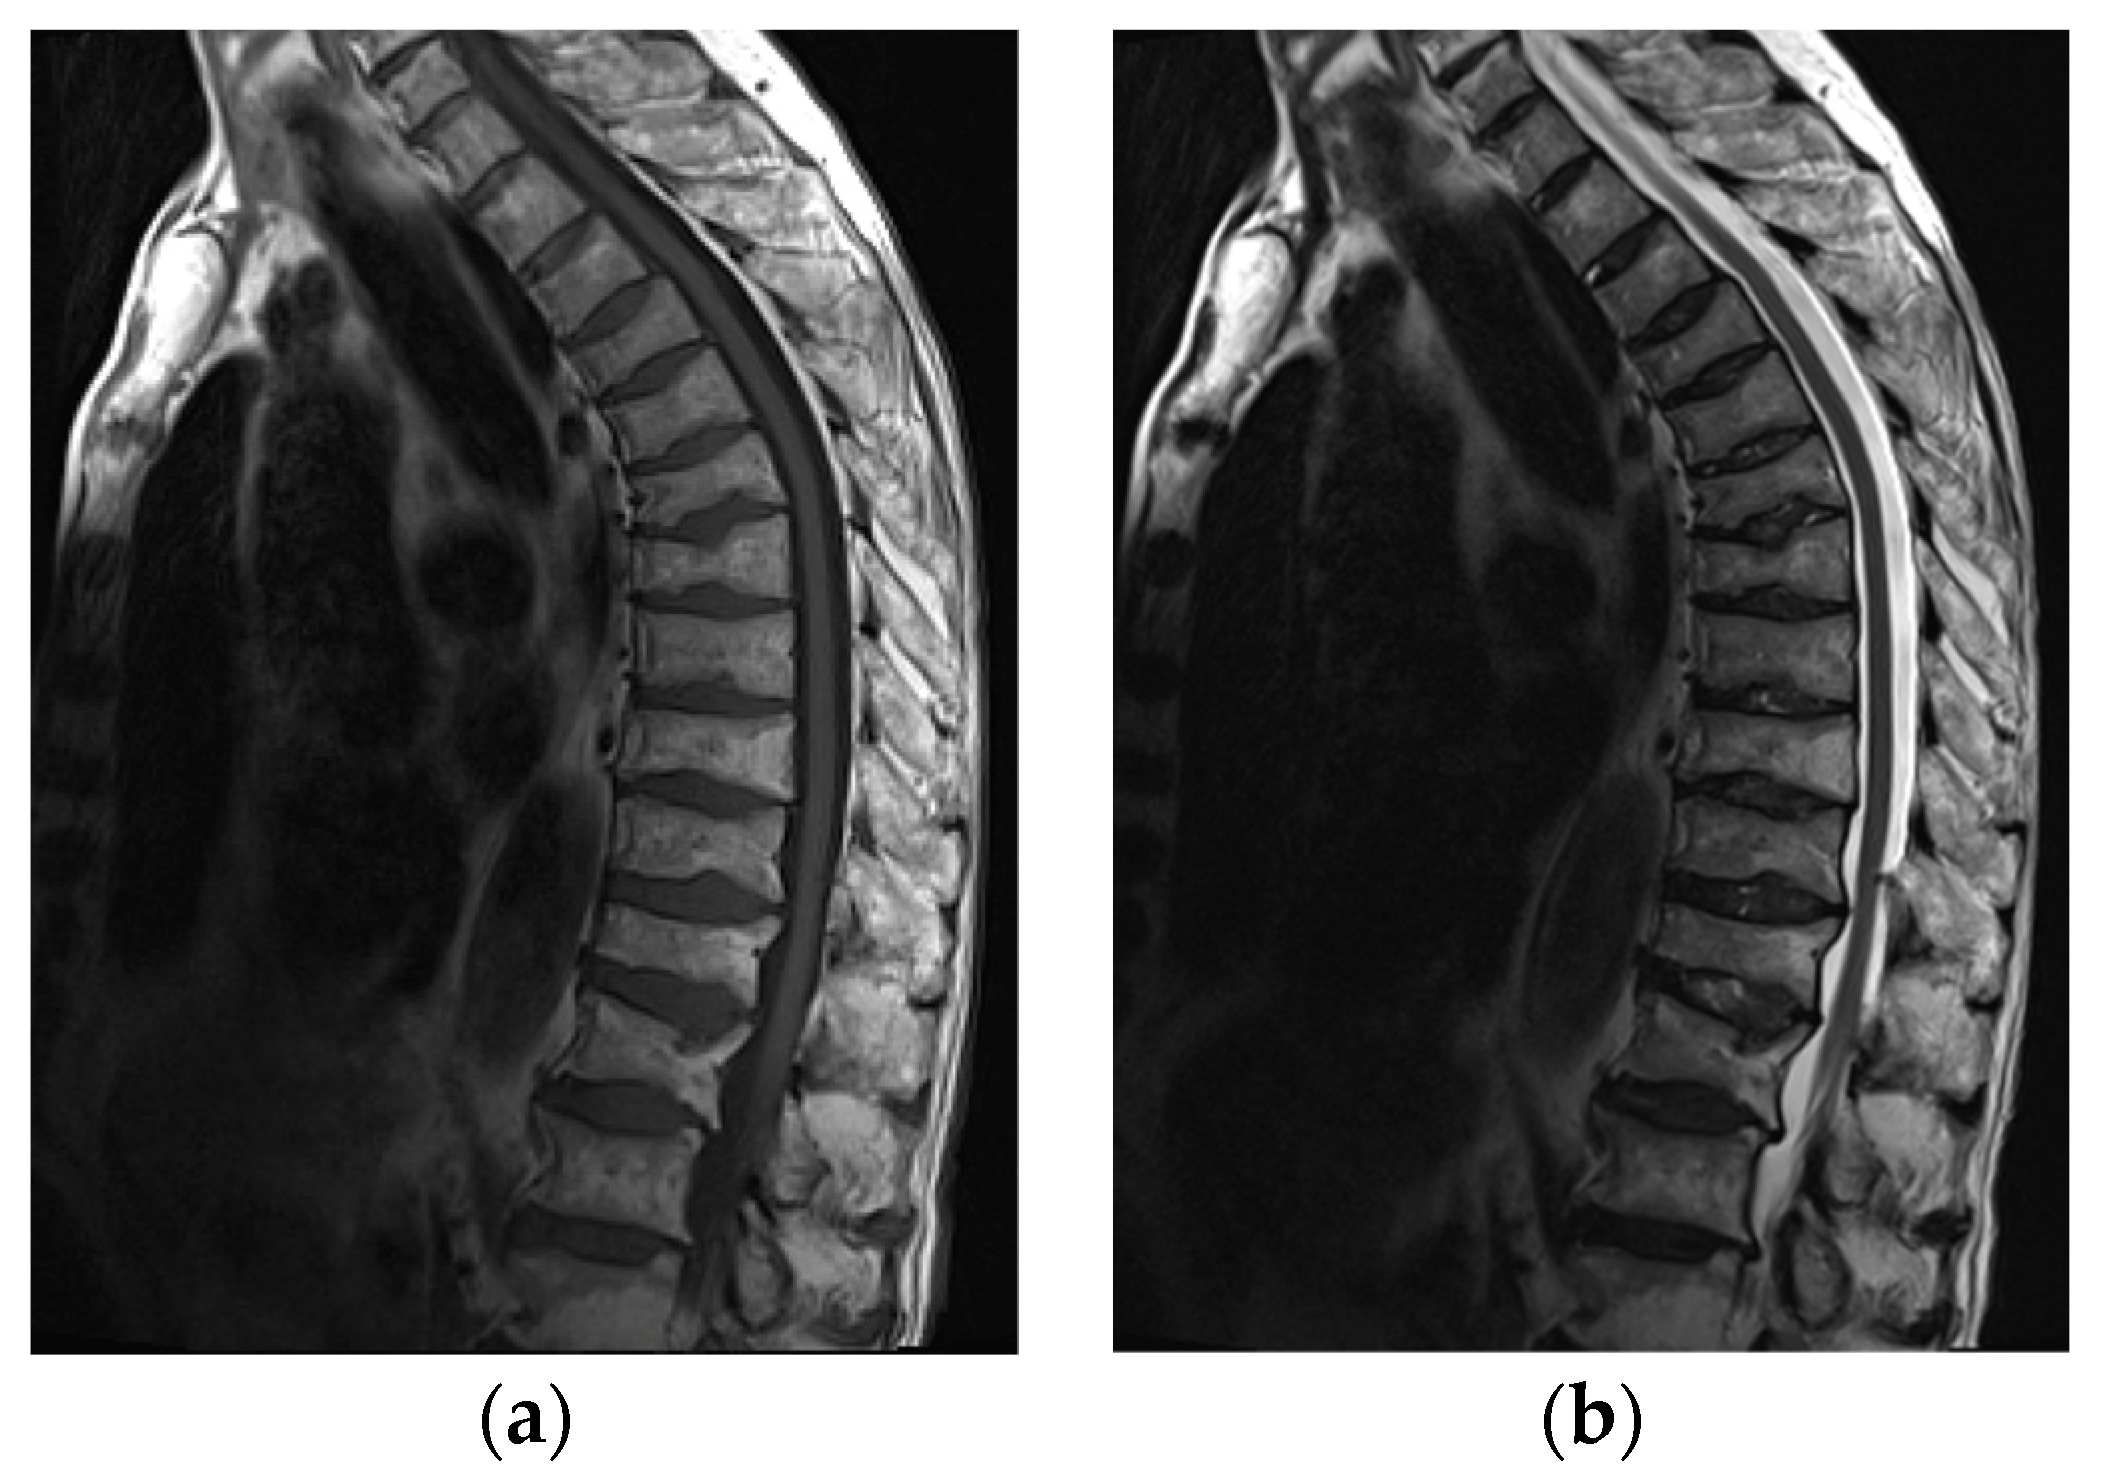

Imaging modalities used in the assessment of osteoporosis include conventional radiography, conventional computer tomography (CT), dual-energy X-ray absorptiometry (DXA), quantitative CT, quantitative US, and MRI [24]. Today, radiography and DXA are the techniques of choice for vertebral fracture identification, whereas CT and MRI are used for characterization (dating and differential diagnosis) [25] (Figure 11).

Figure 11.

MRI of the spine in a 61-year-old patient with systemic lupus erythematosus with multiple compression fractures. (a) Sagittal T1-weighted and (b) T2-weighted Time Spin Echo MR images of the thoracic spine show a loss of height in nearly all thoracic and L1 and L2 vertebral bodies without significant bone marrow edema in (b). This is consistent with chronic compression fractures with associated disc dehydration and marginal endplate osteophytes, but without significant retropulsion.